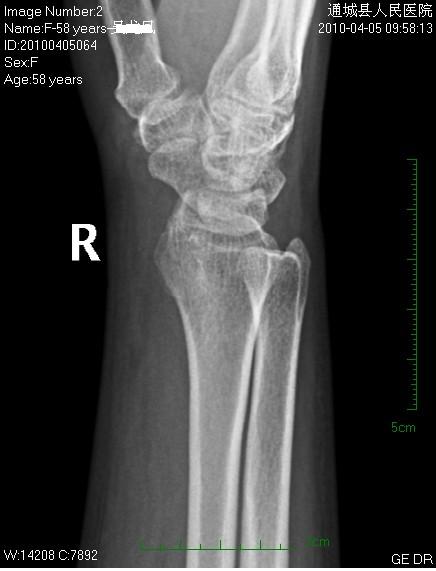

女性58岁,右腕肿痛就诊。平时右腕间断性疼痛,近来加重。

平片见桡前软组织内一密度增高、边缘光整块影

片后查体见右腕、掌轻度肿胀,腕腹侧按压无硬块,自己除有上述征状及类似手癣(痒、小水泡、死皮)外,关节活动无功能障碍。

后三张是透视转动下点片放大。

片含诸构成骨无明显骨质破坏,软组织稍肿胀。片示软组织内异常密度影个人考虑为纤维组织增生,伴局部皮肤呈癣样变。考虑:银屑病性关节炎。建议作进一步检查。

我考虑腱鞘囊肿可能性大。另尺骨稍长,月骨、三角骨尺骨关节面密度减低。考虑尺骨撞击综合症